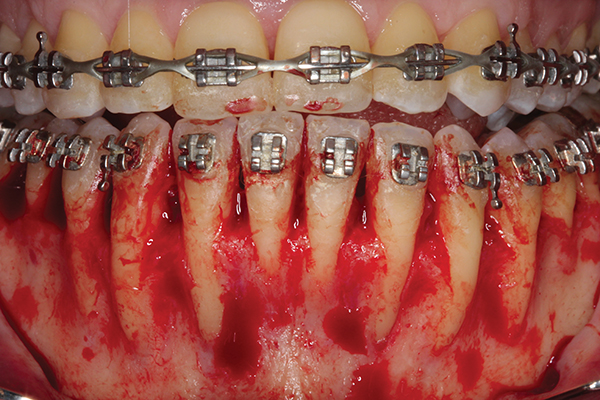

Fig 1. Preoperative SFOT. No loss of attachment, but thin dentoalveolar bone phenotype noted clinically.

Figure 1

Fig 2. Full-thickness flap reflection. Note

dehiscence and fenestrations throughout. Orthodontic walls are limited to nonexistent.

Figure 2

Fig 3. Corticotomy cuts performed.

Figure 3